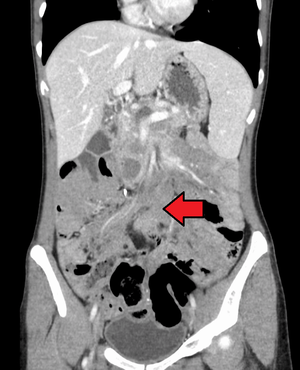

Desmoid tumor as seen on CT scan

Aggressive fibromatosis is a rare condition marked by the presence of desmoid tumors. Desmoid tumors can arise in virtually any part of the body, and are tumors that arise from cells called fibroblasts, which are found throughout the body and provide structural support, protection to the vital organs, and play a critical role in wound healing. These tumors tend to occur in women in their thirties, but can occur in anyone at any age. They can be either relatively slow-growing or malignant. However, aggressive fibromatosis is locally aggressive. When they are aggressive they can cause life-threatening problems or even death when they compress vital organs such as intestines, kidney, lungs, blood vessels, nerves etc. Most cases are sporadic, but some are associated with familial adenomatous polyposis (FAP). Approximately 10% of individuals with Gardner's syndrome, a type of FAP with extracolonic features, have desmoid tumors.[1]

Desmoid tumors may be classified as extra-abdominal, abdominal wall, or intra-abdominal (the last is more common in patients with FAP). It is thought that the lesions may develop in relation to estrogen levels or trauma/operations.